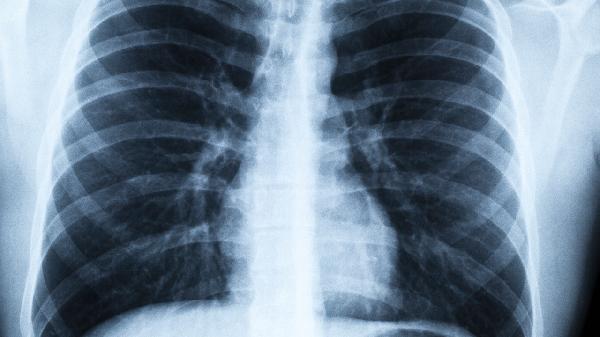

58岁男子肺癌晚期,回家天天抽烟,谁劝都没用:生死看淡?

58岁的老张确诊肺癌晚期后,医生办公室里那盆绿萝的叶子突然晃了晃。他掸了掸烟灰说:“横竖都是个死,不如抽个痛快。”家人轮番.上阵劝说,他却把化验单折成纸飞机,从医院窗口扔了出去。

1、医学数据显示,晚期肺癌患者五年生存率不足15%。但放弃治疗不等于放弃生命,规范镇痛治疗能让80%的患者获得生活质量改善。